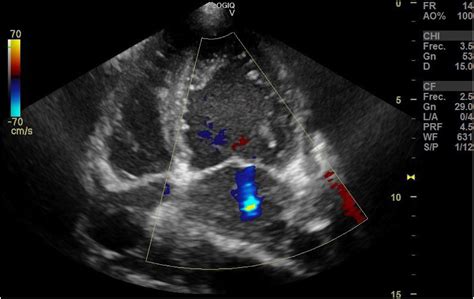

To better understand Non Compaction Cardiomyopathy, it is helpful to visualize the heart's anatomy. Typically, the heart walls are smooth and dense. In patients with NCCM, the myocardium (the heart muscle) remains thin and features excessive trabeculations—small, finger-like projections—and deep inter-trabecular recesses. These structural flaws create a "spongy" appearance when viewed through imaging techniques.

Diagnosing Non Compaction Cardiomyopathy primarily involves advanced cardiac imaging. Physicians utilize specific diagnostic criteria to differentiate NCCM from a normal heart that may just have prominent, yet healthy, trabeculations.

Echocardiogram The first-line imaging test to visualize structure and blood flow.